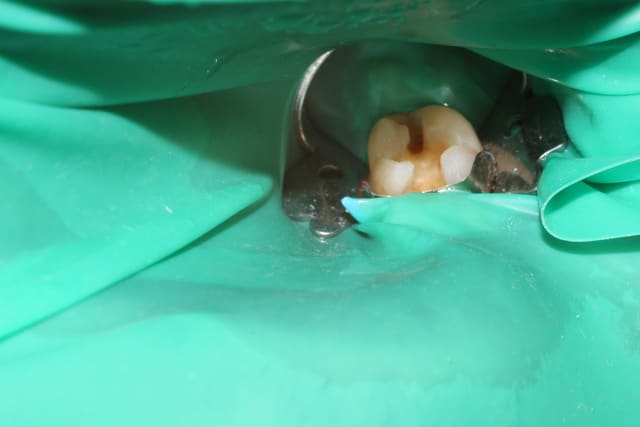

Il a été suggéré que je bossais à la zob. J'ai donc pris des photos des quelques boulots de l'aprem.

Rien de très intéressant, mais je crois avoir déjà posté un certain nombre de cas ici, tous critiquables mais aucun bâclé.

Pour ceux qui n'ont que ça à foutre, vous pouvez les relier aux posts précédents.